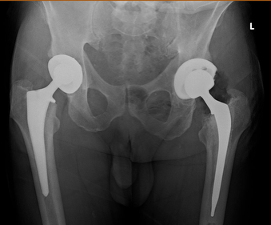

In 2025, revision of the left hip was performed through the previous posterior approach. Intraoperative polyethylene wear pattern revealed evidence of mechanical impingement, posteriorly. Impingement was occurring at 10 degrees of left hip extension. The head and polyethylene liner were exchanged with a size 40 mm Biolox Delta ceramic head and a 40 mm ID / 64 mm OD XLPE liner. No posterior impingement was occurring past 25 degrees of hip extension. Importantly, the VerSys Heritage cemented femoral stem, now 24 years in situ, was well-fixed with excellent cement mantle integrity and was retained (Figure 3).

To date, the patient’s mechanical impingement resolved and he has had no further dislocation events. The cemented VerSys Heritage femoral stem continues to demonstrate stable fixation at 24 years postoperatively, with intact cement mantle and no evidence of loosening or osteolysis.

- During this period, the patient also underwent primary right THA, with DM technology used to mitigate dislocation risk.

Longevity of Cemented Femoral Components. The cemented femoral stem, conceived by Sir John Charnley in the 1960s, continues to demonstrate an excellent track record. In this patient, the cemented stem has provided stable, pain-free fixation for 24 years with no evidence of loosening, subsidence, or periprosthetic osteolysis. This is consistent with registry data and long-term cohort studies demonstrating that well-cemented femoral components can survive three decades or longer.1,2,15 Notably, the stem was retained at the time of revision, requiring only a head and liner exchange, a testament to the enduring reliability of the cemented femoral fixation.